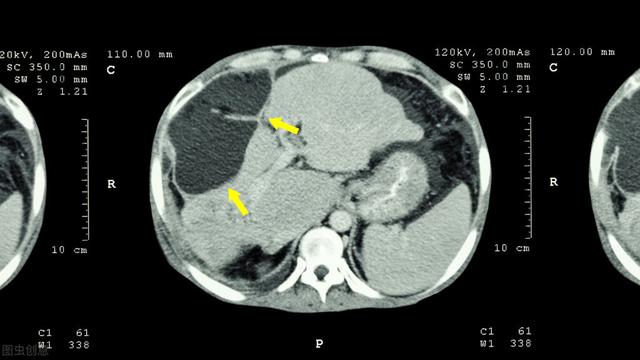

由肝脏引起的肝源性疾病因肝功能受损和门静脉高压导致液体积聚在腹腔内,而形成腹水,是肝硬化最常见的并发症之一,常见于肝硬化失代偿期、肝衰竭、肝脏血管类疾病、自身免疫性肝病、肝病肿瘤等。

一旦患者开始出现肝腹水,就代表肝病已经很严重了。当肝脏受损加重,代谢能力下降,就会使体内的腹水增多。作为正常健康的人,腹腔内的体液其实都会被代谢掉,剩下的不多,如果增多就会形成腹水,由肝脏受损引起的就是肝腹水,这时候一定要尽快就医,避免肝病进一步恶化。

早期的肝硬化患者并不会出现腹水,一旦腹水形成,就表示患者已经进入肝硬化失代偿期,多处于晚期症状了。不仅影响肠胃功能,也会伴有腹痛、排尿次数减少,大便异常,还会有畏寒、低热等状况。